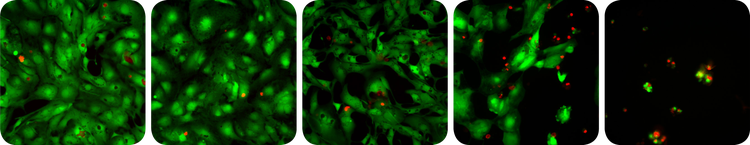

Membrane-permeable Calcein AM is cleaved by esterases in live cells to produce green fluorescence in the cytoplasm. In dead cells, the cell membrane is compromised, allowing the dye, ethidium homodimer, to enter and stain the nucleus (Figure 1).

Cytotoxicity assay- exposed to increasing levels of a toxic compound

***Figure 1. Cytotoxicity assay. *Cardiomyocytes exposed to increasing levels of a toxic compound (left to right). Live cells exhibit green fluorescence and an increasing incidence of red stained dead cells is evident at higher doses.